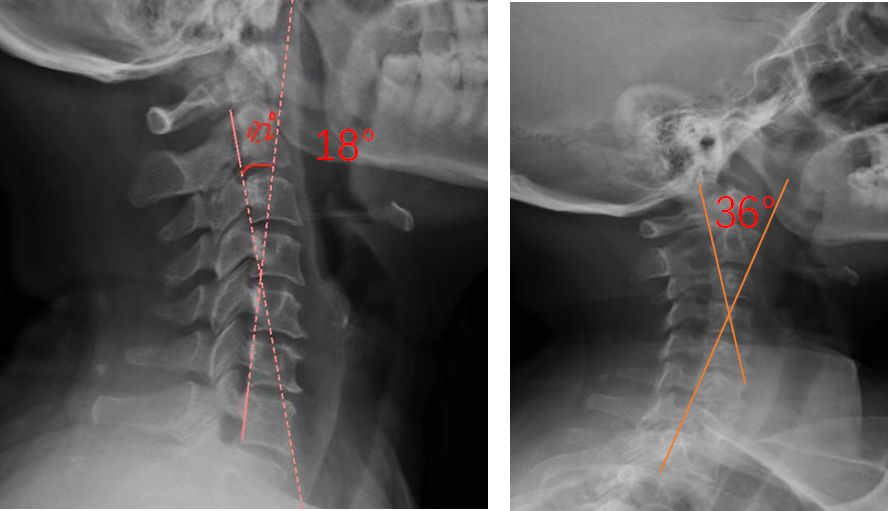

患者适配前后侧位X光,佩戴前18°,适配后36°

对于颈椎病患者,合理设计的颈椎枕,能够紧密适合颈椎,矫正颈椎生理曲度;再根据颈椎曲度改善情况,随时间慢慢调整3D打印颈椎枕曲度,使变直的颈椎逐渐形成正常的生理曲度,改善颈肩痛的症状